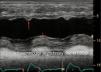

One of the most challenging clinical scenarios to manage in the CPO setting is mitral regurgitation due to abnormal systolic anterior motion (SAM), generating a pressure gradient in the LVOT or mesoventricular region, dragging and sucking the mitral anterior leaflet (Fig. 3). This should be suspected in cases with concentric hypertrophy, myectomy, or large post implantation toward the LVOT, states of hypovolemia, and/or need for ascending vasoactive support without an appropriate tensional response.

Coronary artery bypass graft (CABG) in a patient with concentric LV hypertrophy: dynamic obstruction of LVOT due to excessive inotropic support and postoperative hypovolemia, leading to severe mitral regurgitation due to anterior septal motion (SAM). Note the progressive acceleration flow on the continuous-wave Doppler.